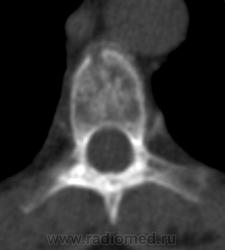

Костное окно:

Я всегда с интересом отношусь к "высоким технологиям", но, как свидетельствуют данные, картинка тел пораженных позвонков при миеломе очень напоминает "картинку мозга"...

По имеющимся файлам-дайком я не нашла признаков опухоли. Имеется множественное остеолитическое поражение позвоночника, ребер, грудины, частично - таза. Лимфоузлы не увеличены. Тоже поставила бы на первое место миеломную болезнь. Диагностирование её не всегда простое дело. Поражена грудина и, наверное, нужно посоветоваться с онкологом (гематологом) стоит ли сделать стернальную пункцию.Советую написать в личку tatyana.